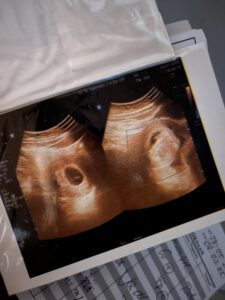

Dan ternyata benar, Tsabina telah hadir disini, berukuran sebesar biji polong. Biji polong yang membuat kami berjuta kali mengucap syukur yang tak terhingga. Dikala itu belum terdengar detak jantungnya, dr menyarankan untuk kembali lagi dua minggu kemudian. Namun benar, kantung kehamilan telah terbentuk. Janin sedang berjuang. Hati kami riang tetapi juga deg-degan menunggu minggu berikutnya.

Usg Tsabina